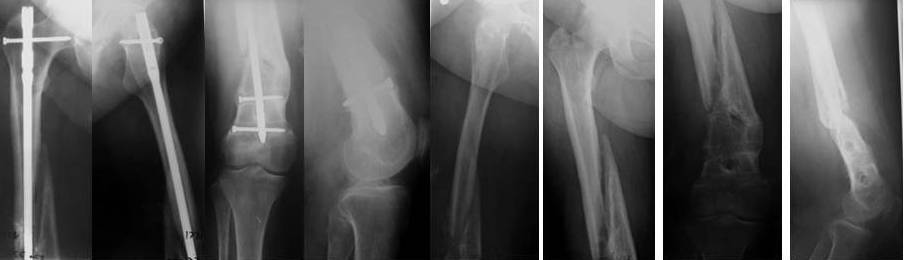

пациентка 58лет, ожирение III СТ., сахарный диабет 2 типа, 3 года назад БИОС бедра в г.Н-ске по поводу перелома в н\3, а теперь красота писаная!!!!! уважаемые коллеги! пациентка 58лет, ожирение III СТ., сахарный диабет 2 типа (субкомпенсированный), 3 года назад БИОС бедра в г.Н-ске по поводу перелома в н\3, нагрузка разрешена на ногу сразу, несмотря на вес, качество и метод остеосинтеза, а теперь красота писанная!! штифт убрали неделю назад с тех. трудностями, есть мнение выполнить, клиновидную остеостомию на уровне деформации, ретроградно с рассверливанием Expert с клинком и костной пластикой. Ваше мнение???С уважением.Керимов Артурцентр травматологии и ортопедии ГВКГ им.Н.Н.Бурденког.Москва

Здесь не видно необходимости пластики. Костную пластику при интрамедуллярном остеосинтезе как-то вообще не приходится делать, разве что речь о замещении сегментарных дефектов.

Антеградный канал уже есть, зачем делать еще и ретроградный. Канал рассверлить и взять гвоздь уже серьезного диаметра, от 12 мм. Но здесь одна серьезная проблема - вальгус. Наверно (надо скиаграмму сделать и уточнить) просто изменением оси его не устранить, потому что промежуточный отломок по медиальной стороне сросся с периферическим под углом, он не даст правильно расположить мыщелки бедра к диафизу.

Для восстановления оси достаточно поперечной остеотомии дистального отломка по нижнему краю центрального. В периферическом отломке ввести

спереди назад отклоняющие спицы или винты, чтобы гвоздь пошел не по старому каналу, а куда надо. Приблизительная схемка в приложении.

Гвоздь надо запереть в дистальном отломке более чем 2 винтами. Лучше, чтобы и винты были потолще.

Не получилось послать снимки в нормальном качестве, но реально- каналы от удаленных винтов в дистальном фрагменте толщиной до 2.0см, выраженный остеопороз, "вальгус" на скиаграмме -25гр. Рекурвация- 20гр.

Для дистальных переломов бедра и при сопутствующем ожирением мы бы предпочли ретроградную фиксацию антеградной.

При восстановленной оси можно штифтовать как описали коллеги, предпочтительно антеградно более мощным гвоздем.

Множественные винты под разными углами лучше гарантируют стабильность в дистальном отделе бедра, чем один большой спиральный клинок Expert.

Без имплантатов с угловой стабильностью при порозности костей невозможно создать стабильность в дистальном отделе бедра, и направленные в одной плоскости блокирующие винты не всегда контролирируют варусно-вальгусные деформации.

Стабильность можно добится блокировкой спирального (Synthes) клинка болтом через коленный сустав или вместе огромного мыщелкового винта предпочтительно несколькими винтами в косом направлении (Stryker Nail). При отсутствии их, откляняющими Poller спицами или винтами по усмотрению.